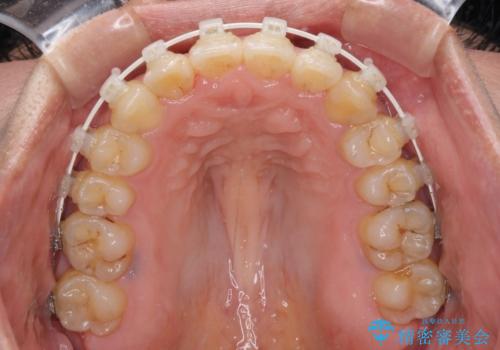

- 矯正装置

- 審美装置

治療開始後すぐに妊娠され、つわりと闘いながらの矯正治療となりました。

上下顎でゴムかけを行ったのですが、早く終わらすためにしっかりと装着していただき、無事出産前に装置を外すことができました。